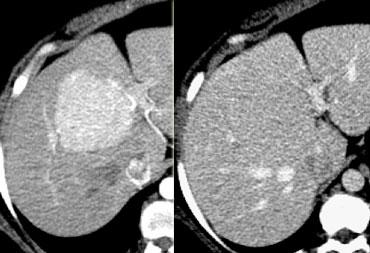

CT sẽ cho thấy U tăng sản nốt khu trú (FNH) là một khối u giàu mạch máu, tăng tỷ trọng trong thì động mạch, ngoại trừ sẹo trung tâm.

Bên trái là hình ảnh điển hình của FNH với sẹo trung tâm giảm tỷ trọng trong thì tĩnh mạch cửa và tăng tỷ trọng trong thì cân bằng.

FNH seen as hypervascular lesion in the late arterial phase and isodense to normal liver in the portal venous phase. No scar was seen.

Chẩn đoán FNH dựa trên việc xác định sẹo trung tâm và sự tăng quang đồng nhất.

Tuy nhiên, sẹo trung tâm điển hình có thể không quan sát thấy ở tới 20% bệnh nhân (hình).

Chìa khóa để chẩn đoán tổn thương bên trái là thực tế tổn thương này đồng tỷ trọng với nhu mô gan bình thường trong thì tĩnh mạch cửa và duy trì như vậy mà không có hiện tượng thải thuốc trong thì muộn (không hiển thị).

Đây cũng có thể là u tuyến, nhưng ung thư biểu mô tế bào gan khó có khả năng xảy ra vì chúng thường biểu hiện thải thuốc nhanh.